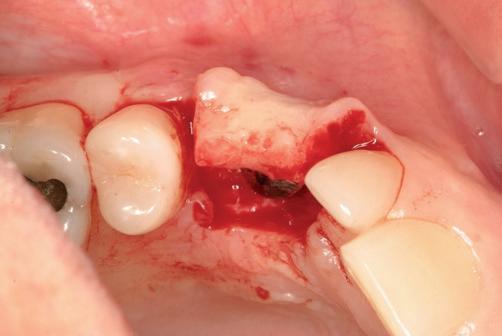

Implantologische behandelingen in het esthetische front vragen meer dan technische vaardigheid alleen. Ze vragen om overzicht, timing, vertrouwen en een team dat als vanzelf samenwerkt onder druk. Juist bij complexe casussen, waarin angst, infectie en hoge esthetische verwachtingen samenkomen, wordt zichtbaar hoe bepalend de rol van de tandartsassistent is.

Deze casus beschrijft een uitgebreide immediate implantaatbehandeling bij een patiënt die door meerdere collega’s werd geweigerd. Niet omdat de mogelijkheden ontbraken, maar omdat de complexiteit vroeg om een perfect afgestemde samenwerking. Het verhaal laat zien hoe de assistent in zo’n traject veel meer is dan een uitvoerende kracht of “mal”, maar een dynamische surgical guide die het proces mede stuurt, bewaakt en mogelijk maakt.De patiënt: wanneer alles samenkomt

Ze kwam binnen op een dinsdagochtend, iets voor achten. Een vrouw van begin zeventig, met een zachte stem en ogen die meer vertelden dan haar woorden. Ze vertelde dat ze een eigen B&B had en dat ze zich nauwelijks kon voorstellen gasten te ontvangen zonder tanden. Op dit moment kon ze echter nauwelijks lachen. “Het doet pijn… en het ruikt soms ook niet goed,” zei ze bijna verontschuldigend. Haar oude bovenbrug, die ze al meer dan twintig jaar droeg, was langzaam maar zeker ingestort. Er was sprake van cariës onder meerdere pijlers, pusafvloed,

chronische ontsteking en een brug die mobiel was en elke beet pijnlijk maakte. Ze had inmiddels meerdere tandartsen bezocht. Drie hadden haar geweigerd. Te complex. Te veel wensen. Te onvoorspelbaar.

De kern van haar vraag was eenvoudig en tegelijkertijd uitdagend: Is het mogelijk om mijn huidige brug te dupliceren en een nieuwe brug te vervaardigen met minder complicaties?

De basis van een complexe beslissing

Mijn behandelplan begint altijd met een uitgebreid klinisch onderzoek. Dat omvat een medische anamnese, intra- en extra-orale camerafoto’s en uitgebreid verwachtingsmanagement. In deze fase is mijn assistent vooral bezig met het zorgvuldig vastleggen van alle gegevens. Juist dat nauwkeurig documenteren zorgt voor rust in de behandelkamer. Minstens zo belangrijk is het luisteren naar de patiënt. Niet alleen naar de klachten, maar naar het

levensverhaal en de mens achter de brug. Begrijpen wat deze behandeling voor iemand betekent, is cruciaal voor het uiteindelijke succes.

Na het klinische onderzoek volgde het röntgenologisch traject. De CBCT liet precies zien wat we al vreesden: een front waarin het bot onregelmatig was, duidelijke radiolucenties rond de pijlers en een infectiegebied dat zich onder vrijwel de gehele brug had verspreid. Tegelijkertijd was er ook potentie. Net voldoende botstructuur om immediate implantaatplaatsing te overwegen, mits alles perfect gepland zou worden.